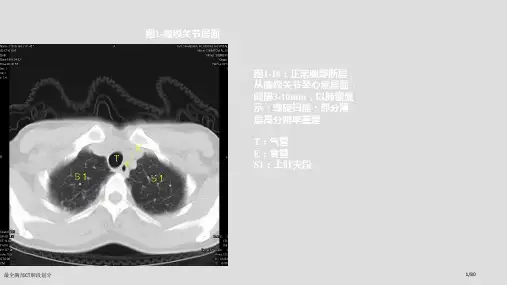

“独眼能看双上肺,左下还留一点背”:

指气管层面,能显示两上肺,在偏下方层面,能看到左肺下叶背段

独眼能看到双上肺,左下还留一点背。

指气管层面,能显示两上肺,在偏下方层面,能看

指气管层面,能显示两上肺,在偏下方层面,能看到左肺下叶背段。